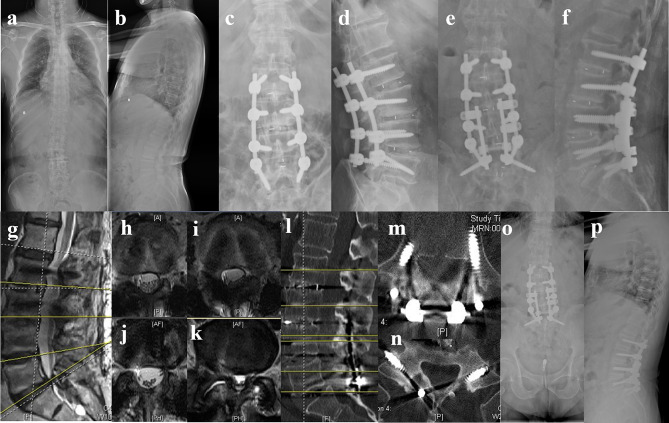

Patients and methods: From January 2018 to December 2019, a total of 41 patients of mild adult degenerative scoliosis with stenosis underwent posterior lumbar decompression, bone graft fusion, and internal fixation, which were retrospectively divided into pedicle screw (PS) group and cortical bone trajectory (CBT) screw group according to different internal fixation methods. The operation time, intraoperative blood loss, immobilization, and length of hospital stay were compared between the two groups. The visual analog score (VAS) of low back and leg pain, Oswestry disability index (ODI), Cobb angle, lumbar lordosis (LL) angle, apex vertebral translation (AVT), coronal balance distance (CBD) and sagittal vertical axis (SVA) were compared between the two groups preoperatively and 6 months, 1 year, 5 years postoperatively. Perioperative and follow-up complications were observed.

Results: The CBT group was superior to PS group in operation time, intraoperative blood loss, immobilization, length of hospital stay (P<0.05). The low back VAS and ODI in CBT group were significantly lower than those in PS group at 6 months, 1 year and 5 years postoperatively (P<0.05). The leg VAS in CBT group was lower than PS group at 5 years postoperatively (P<0.05). The incidence of screw loosening and adjacent segment disease 5 years postoperatively in CBT group was significantly lower than that in PS group (P<0.05).

Conclusion: Multi-segment cortical bone trajectory screws is a safe and effective treatment option for mild adult degenerative scoliosis with stenosis among the elderly. This technique features miniinvasive trauma and quick recovery, which might lead to improved long-term quality of life and a reduction in screw loosening and adjacent segment disease rates.